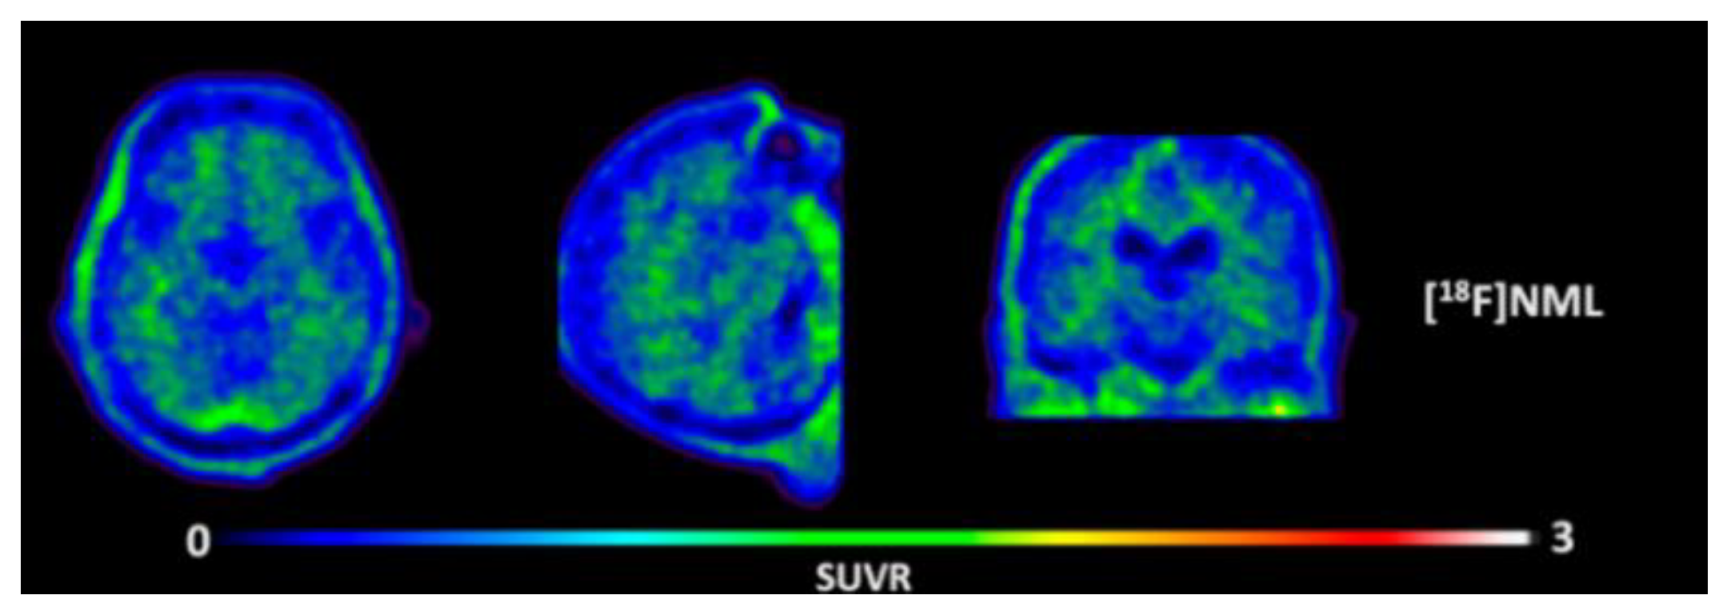

Figure 6.

Representative transversal, sagittal, and coronal (18F)N-methyl lansoprazole (NML) PET images in a progressive supranuclear palsy patient for the detection of tau [70]. Images are reprinted with permission of the publisher [70].